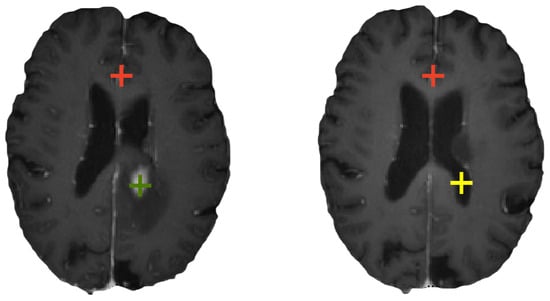

2.1. Problem Statement

2.2. Bidirectional Registration Framework